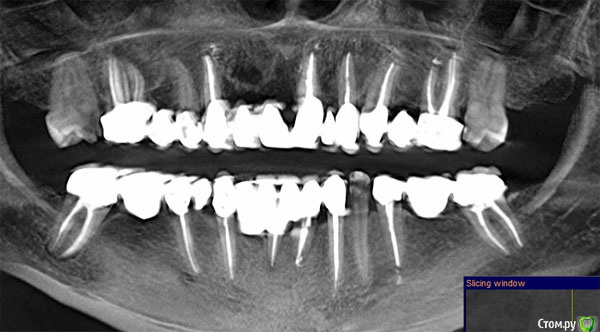

It'sGeorgy Опубликовано 12 мая, 2020 Поделиться Опубликовано 12 мая, 2020 (изменено) ну если прямо сильно нажимаю на него то ощющение небольшой боли вроде есть, а так кушать не больно им, а что скажите по кт, я в срезах не понимаюНа КТ, действительно, есть очаг разрежения костной ткани вокруг этого зуба. При этом, сказать, что каналы запломбированы плохо - тоже нельзя. Я не терапевт, но со своей точки зрения вижу ситуацию так, что у зуба, на самой вершине, есть достаточно выраженный изгиб, что создало огромную трудность для доктора, который зуб лечил. Этот изгиб, к сожалению, запломбировать ко конца не получилось, что привело к развитию хронического воспаления.Повторюсь, я подобным лечением не занимаюсь и мое мнение может быть ошибочным. Поэтому, предлагаю подождать, пока вам ответит кто-то из здешних терапевтов. это не может быть от зуба?Такие ситуации могут быть от зуба, но тогда боль острая и постоянная. Плюс, тогда пациент сам может определить, что его беспокоит конкретный зуб. В вашем случае, как я понимаю, такого нет. Да и судя по снимку, остальные верхние зубы слева в порядке. делала кт 3 раза за годЕсли есть возможность, выкладывайте их тоже. Потому, что на снимке, который вы выложили очень много фоновых шумов, которые создают металлические конструкции во рту(мостовидные протезы). Возможно, по снимкам до изготовления постоянных конструкций будет видно и понятно лучше. Изменено 12 мая, 2020 пользователем It'sGeorgy Ссылка на комментарий

It'sGeorgy Опубликовано 13 мая, 2020 Поделиться Опубликовано 13 мая, 2020 (изменено) Скажите а штифт не помешает для ретроградного пломбирования, или его надо как то убирать? Штифт ставится не на всю длину канала, поэтому вряд ли он помешает. Выделил его красным на прикрепленном снимке. я нашла кт за март 2019 года, сейчас дам вам ссылку, это до протезирования. Сохраните этот снимок куда-нибудь отдельно, чтобы не потерять его. Он четче и информативнее. Изменено 13 мая, 2020 пользователем It'sGeorgy Ссылка на комментарий